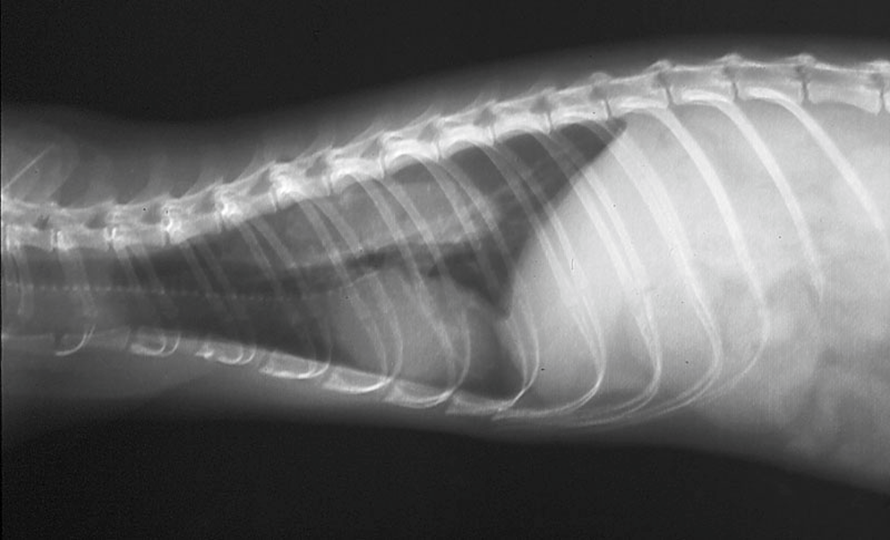

X線検査で食道が拡大(拡張)し、正常な運動性が欠如している状態を指しますが。

鑑別診断には食道または胃腸の異物、胃炎、および呼吸器疾患が含まれます。X線検査では食道が拡張あるいはガスが貯留しており、確定診断のために硫酸バリウムまたはイオヘキソール(経口投与 [PO] で 8~10 mL/kg)を投与します。フェレットは注射器で強制的にバリウムを摂取しますが、食道破裂の可能性がある場合には、バリウムの代わりにイオヘキソールを使用します。造影剤が食道の輪郭を描出し、巨大化していることで診断されます。

造影剤が食道全体に浸潤しているような像が得られると食道炎を併発している可能性が高いです。